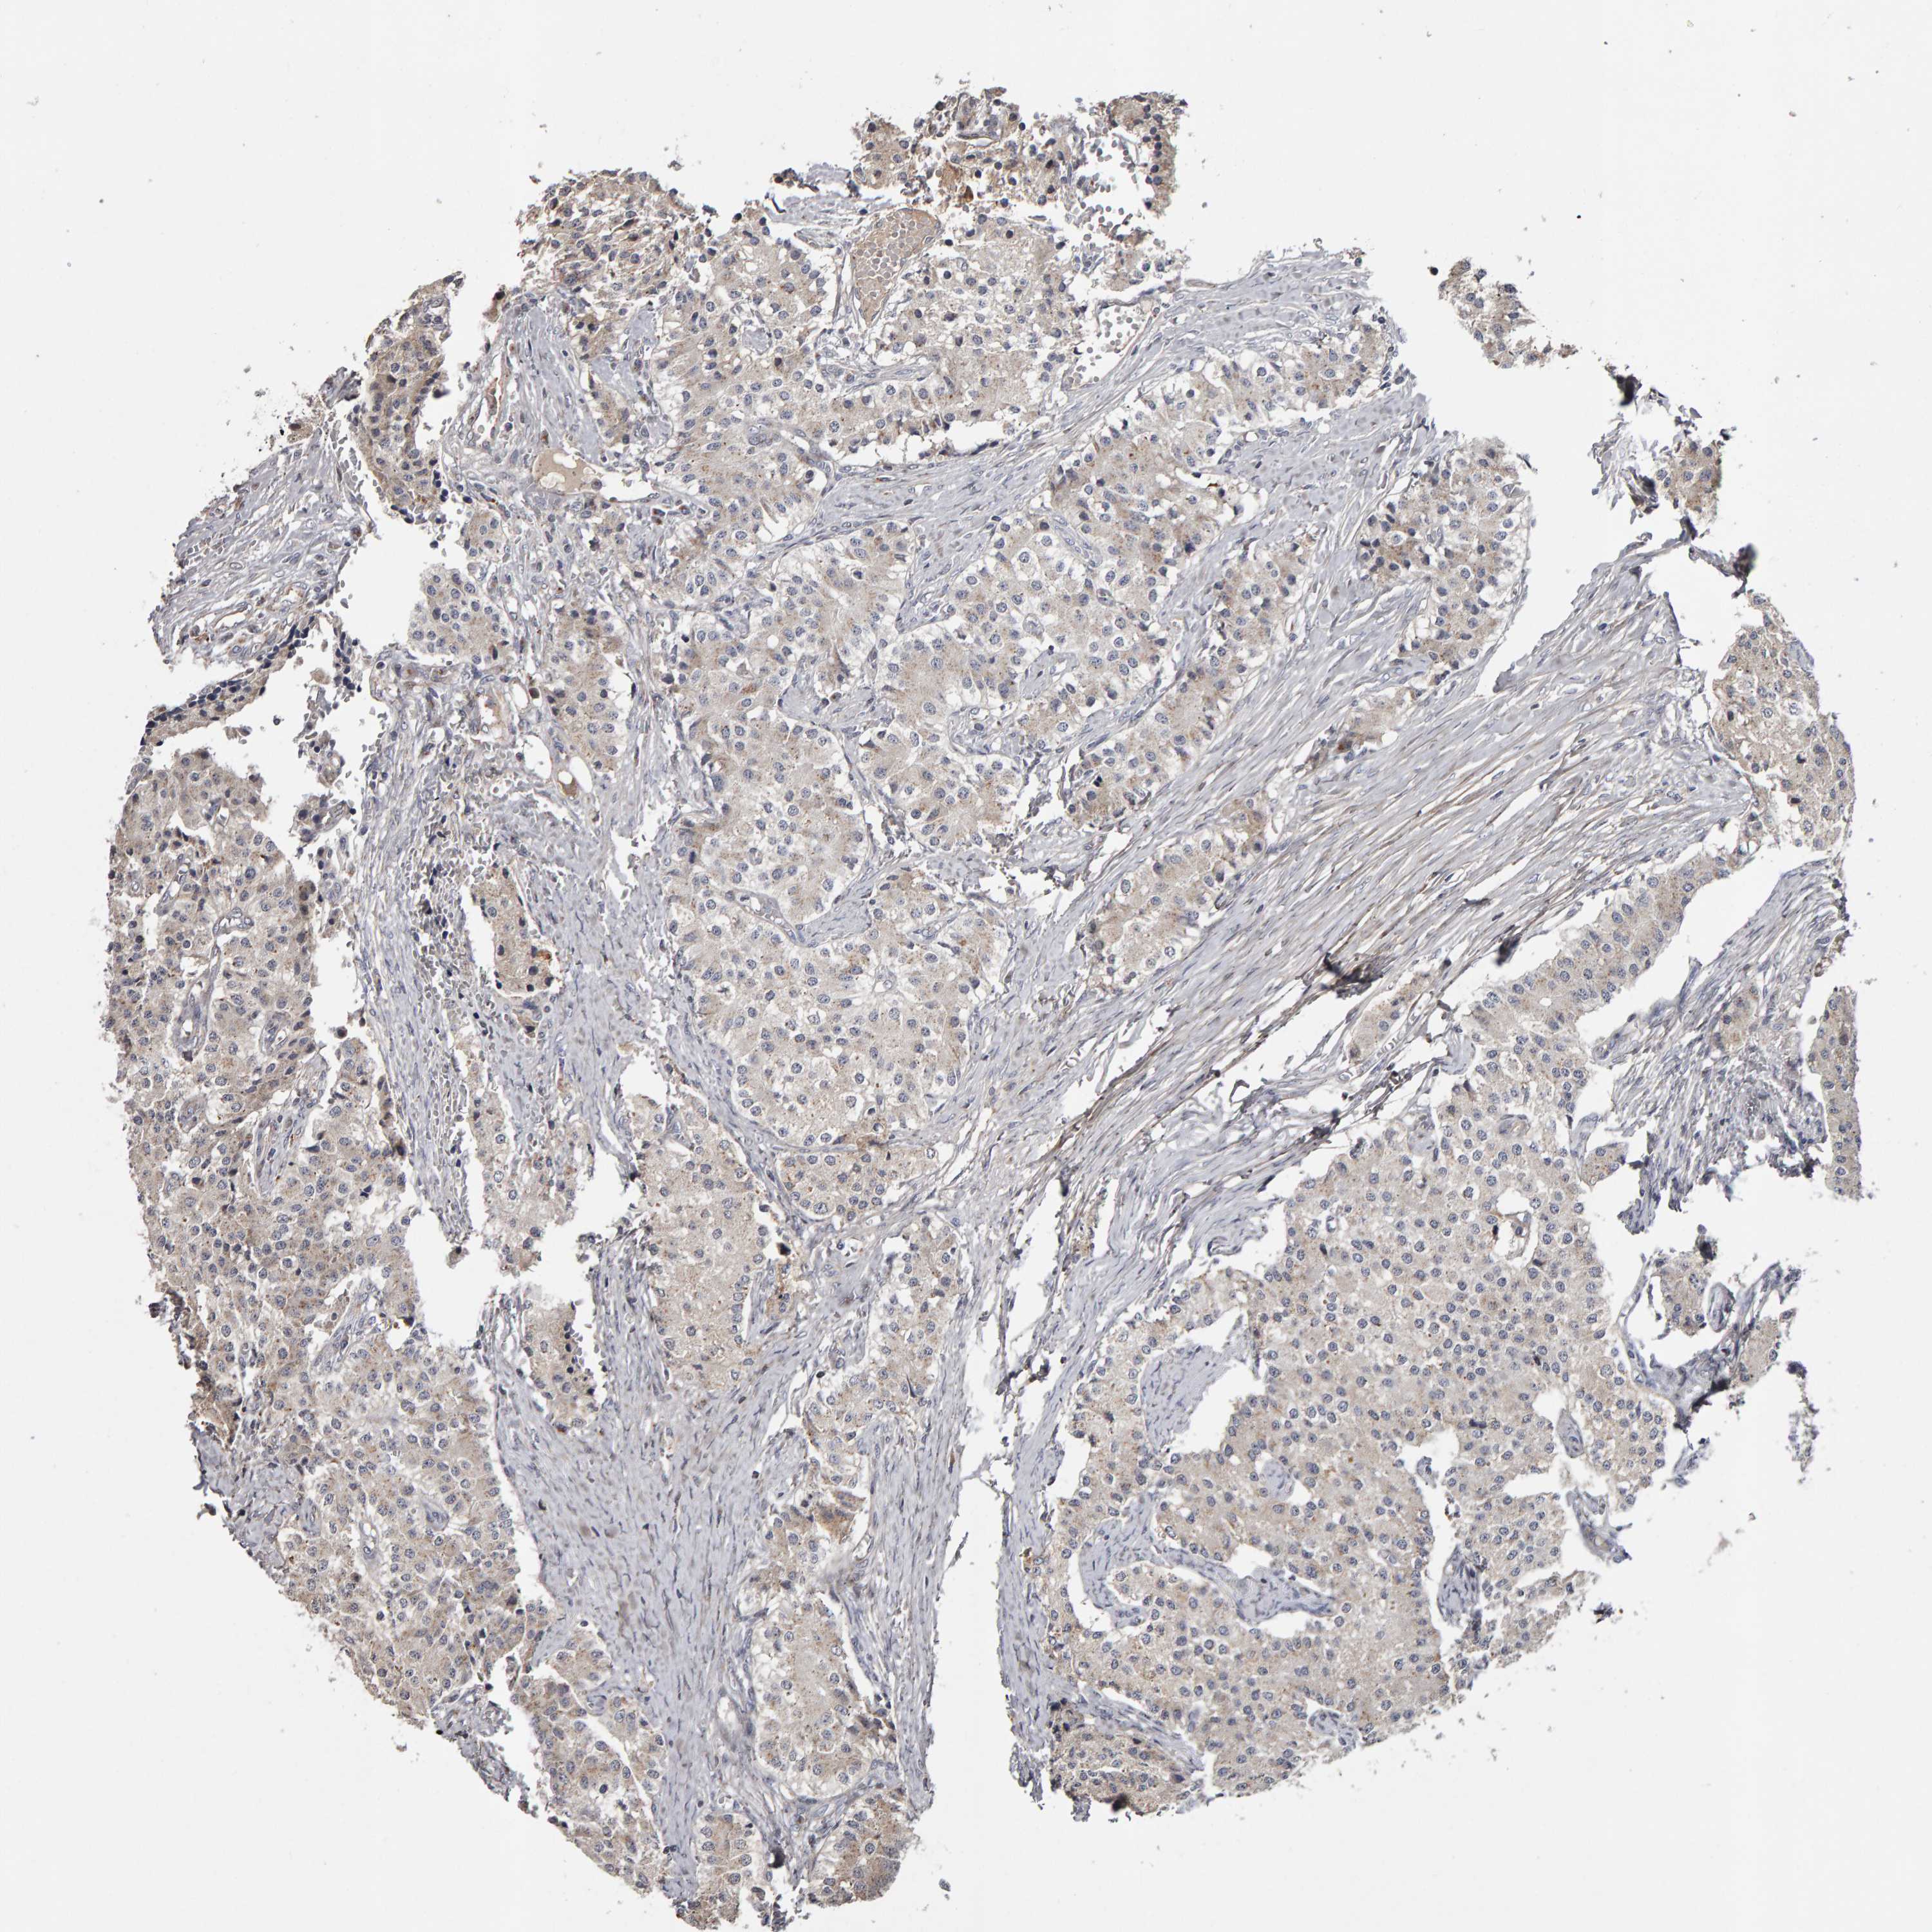

CANT1